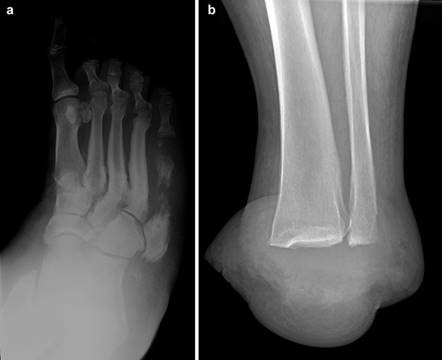

Weight-bearing anteroposterior (AP), lateral, and sesamoid axial radiographs are mandatory. On the AP view, the surgeon measures the Hallux Valgus Angle (HVA, normal < 15°), the Intermetatarsal Angle (IMA, normal < 9°), and the Distal Metatarsal Articular Angle (DMAA). The lateral view is scrutinized for Meary's angle (talo-first metatarsal angle) to identify midfoot collapse, as well as the presence of dorsal osteophytes indicative of hallux rigidus. The sesamoid axial view is critical for assessing the degree of sesamoid subluxation and the integrity of the crista.

In cases of end-stage hallux rigidus, first MTP arthrodesis yields excellent, predictable outcomes. A dorsal longitudinal incision is made just medial to the EHL tendon. The joint is exposed, and aggressive cheilectomy is performed to remove all dorsal, medial, and lateral osteophytes. The remaining articular cartilage on the metatarsal head and the base of the proximal phalanx is resected using cup-and-cone reamers, which allow for infinite adjustment of the joint position prior to fixation.

Positioning of the fusion is the most critical step of the operation. The hallux must be positioned in 10-15 degrees of valgus, 15-20 degrees of dorsiflexion relative to the first metatarsal, and neutral rotation. Excessive dorsiflexion causes shoe impingement, while insufficient dorsiflexion leads to vaulting during gait and interphalangeal joint arthritis. Fixation is most reliably achieved using a pre-contoured dorsal locking plate combined with a lag screw crossing the fusion interface.

For hallux rigidus, Coughlin and Shurnas developed the definitive clinical and radiographic grading system that remains the international standard for guiding treatment. Their research definitively proved that while cheilectomy provides excellent relief for Grades 1 and 2, first MTP arthrodesis is the only reliable, long-term solution for Grade 3 and 4 disease. These landmark studies form the bedrock of modern foot and ankle surgical training, ensuring that orthopedic surgeons approach first metatarsal pathology with a nuanced, evidence-based perspective.